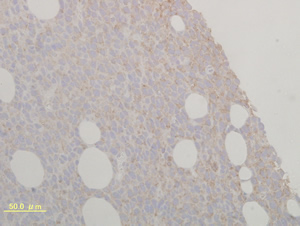

IL-23染色

ラット腫瘍 IL-23